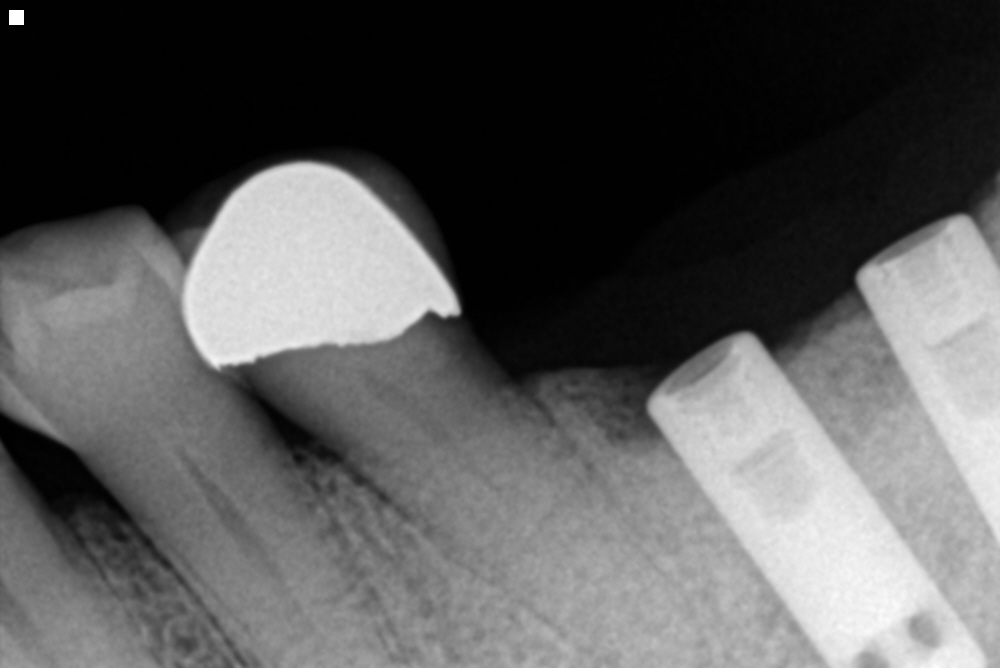

Dental implant screw fracture? How do you fix the problem? Dental Implant Screw Broke Off — if it is the prosthetic abutment that broke off and part of the screw is wedged or stuck in the implant body itself,. — most published articles will discuss that if there is a fractured implant screw, the treatment option is to retrieve the screw or to. Read our guide on immediate steps to take and how. Dental Implant Screw Broke Off.